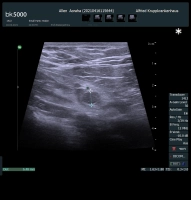

Eine akute Appendizitis kann je nach Ausprägungsgrad in eine unkomplizierte und eine komplizierte Appendizitis eingeteilt werden. Nach der EAES (European Association of Endoskopic Surgery) ist eine unkomplizierte Appendizitis eine Entzündung der Appendix ohne Hinweis auf Gangrän, Umgebungsphlegmone, freier purulenter Flüssigkeit oder Abszess.

Die Einteilung einer akuten Appendizitis in die unkomplizierte oder komplizierte Form soll prätherapeutisch vorgenommen werden, um eine adäquate Therapie auszuwählen.